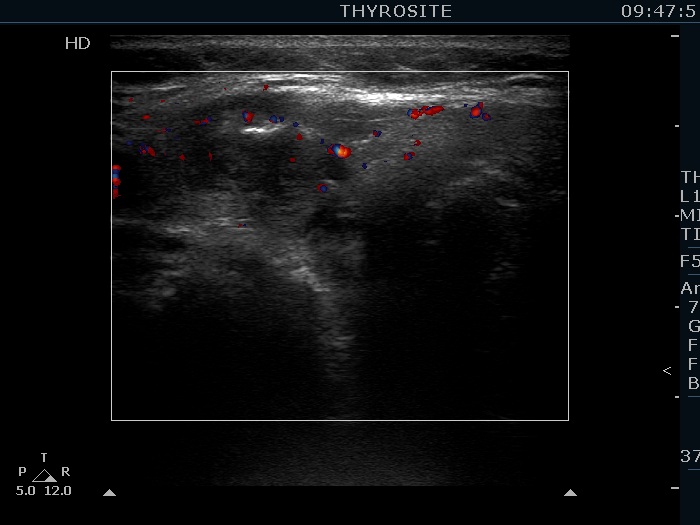

Intranodular hyperechogenic figures - case 1425 (ultrasonographic picture 8)

Upper part of the right lobe, transverse view, color Doppler mode. The vascularization is not specific.